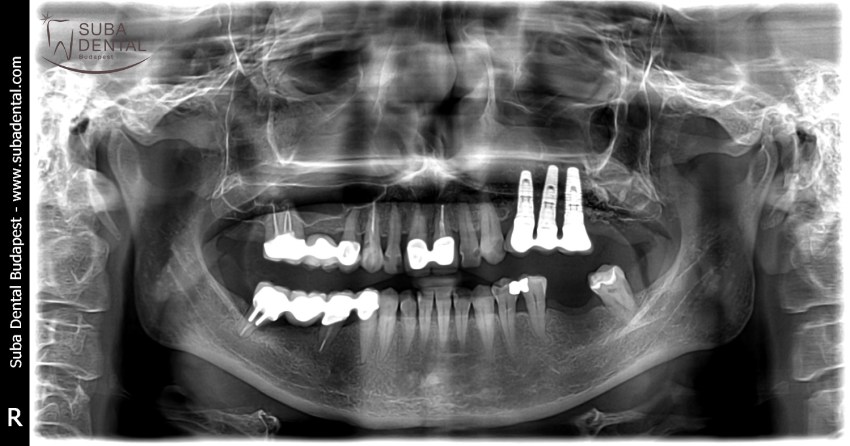

Follow-up panoramic radiograph following the installation of implants. Our patient would have needed a bone graft but was completely inconvincible. Therefore, a total of 4 implants were installed per jawbone that would support a bar denture. The dental foci and infections totally destroyed bone width and bone height as a result of which the mounting of implants required great effort and could only be carried out in an asymmetric fashion.

Panoramic radiograph of the lower and upper bar